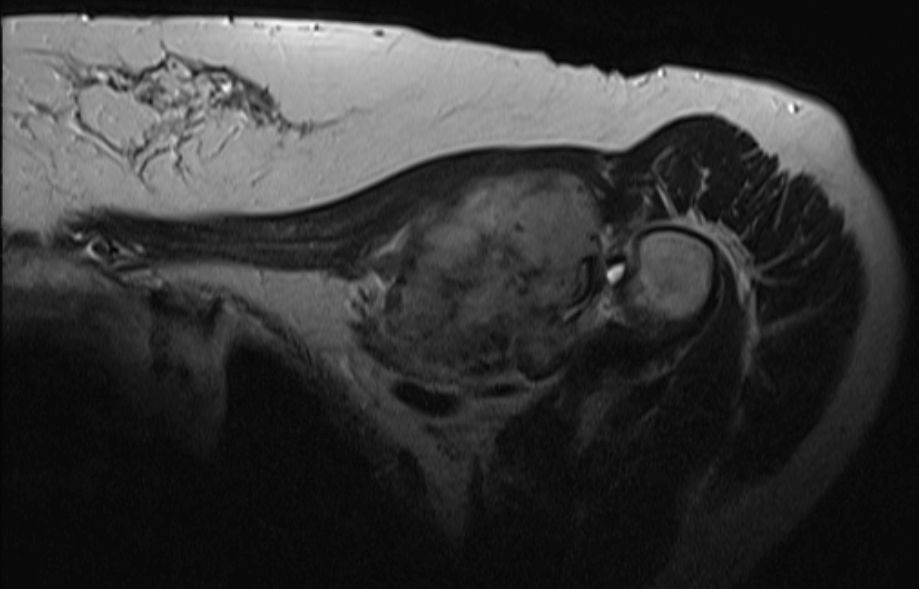

| Diagnostik | 56-jährige Frau mit einer derben, wenig verschieblichen Tumorbildung untergalb der linken Clavikula. ![]() |